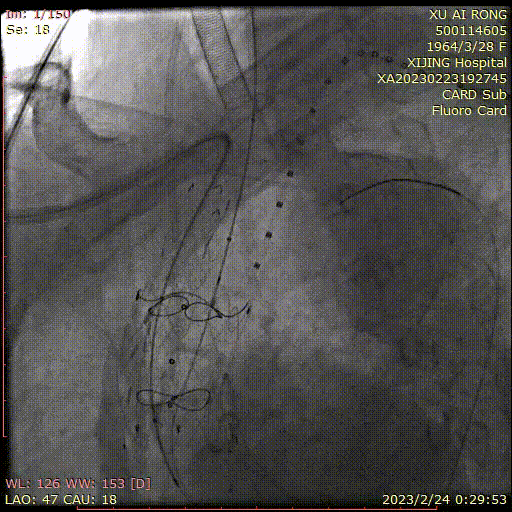

★ 病例4

王某,女,56岁,“突发胸背痛15小时”入院,主动脉CTA提示:升主动脉-腹主动脉管腔外可见新月形低密度影,主动脉弓前部可见溃疡,大小约0.6cm。

术前CTA

术前造影

术后造影

手术用时 95分钟